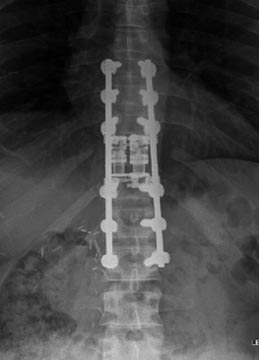

21 year old woman with very ridged 90 degree Scheuremann's kyphosis corrected to 40 degrees.